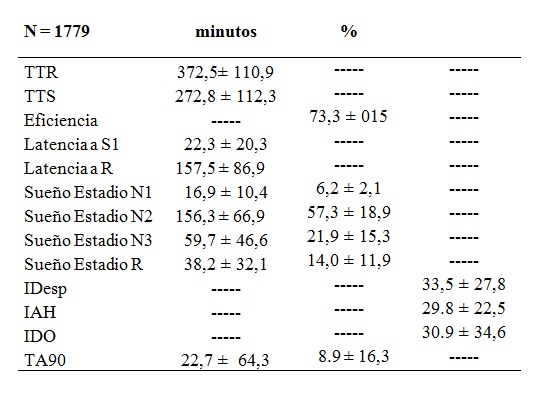

Tabla 9 Estructura del sueño y eventos respiratorios en pacientes con SAHOS

Tabla 9. TTR: tiempo total de registro desde “luz apagada” hasta “luz prendida”; TTS: tiempo total de sueño; Latencia a S1: tiempo desde “luz apagada” hasta el comienzo de S1; Eficiencia del sueño: TTS/TTR (%) Latencia a REM: tiempo desde “luz apagada” hasta el sueño REM; Estadio N1: sueño superficial; Estadio N2: sueño superficial con husos y complejos K; Estadio N 3: sueño profundo; Estadio R: sueño con movimientos oculares rápidos; IDesp: índice de microdespertares por hora de sueño; IAH: índice de apneas+hipopneas por hora de sueño; IDO: índice de desaturaciones cortas > 3% por hora de sueño; TA90: tiempo acumulado con SpO2 <90%.